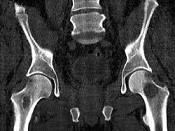

问题 男,46岁,双髋部疼痛,实验室检查血钙升高,尿本周蛋白(+),结合图像,最可能的诊断是?(?)

选项 A.骨髓瘤 B.骨质疏松症 C.骨转移瘤 D.骨囊肿 E.动脉瘤样骨囊肿

答案 A